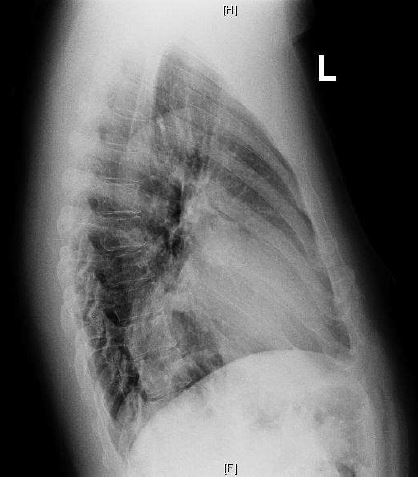

Case Presentation: A 44-year-old man with no known medical conditions presented with acute, painless, left monocular blurred vision. There was no history of smoking or illicit drug use. Physical examination indicated blood pressure of 200/135 mmHg, heart rate 86/min and unremarkable cardiopulmonary exam. Fundoscopic examination showed branched retinal vein occlusion. Patient had elevated Troponin I. Electrocardiogram had pathologic Q-waves in inferolateral leads. Chest X-ray displayed a retro cardiac opacity. Patient was initially managed for hypertensive emergency. Transthoracic echocardiogram (TTE) showed an ejection fraction of 25-30% with dyskinesis and outpouching of basal inferolateral wall concerning for possible pseudoaneurysm with thrombus. A subsequent transesophageal echocardiogram (TEE) confirmed a LV inferolateral PSA with chronic thrombus. Cardiac MRI was remarkable for a 4.6-cm x 6 cm x 5.6 cm PSA with a 3 cm neck and chronic thrombus. Coronary angiography with left ventriculogram showed two-vessel disease (60% proximal LAD and 100% distal RCA) with collaterals and LV outpouching equivocal for pseudo vs true aneurysm. Neck of the aneurysm was not visualized.